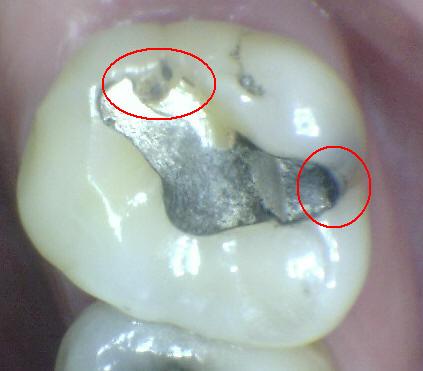

Código 4

(Caries Moderada): Sombra oscura

de dentina subyacente al esmalte intacto con o sin interrupción

localizada del esmalte

- La superficie de los dientes

puede tener características de código 2 y tiene una

sombra de dentina con cambio de color que es visible a

través de una superficie de esmalte aparentemente

intacto o con ruptura localizada en el esmalte pero sin

dentina visible. Este aspecto se ve más fácilmente

cuando el diente está húmedo y es una sombra oscura e

intrínseca que puede ser de color gris, azul, naranja o

café.

- Nota: observar el diente húmedo y luego seco. Esta

lesión debe distinguirse de sombras ocasionadas por

amalgama.